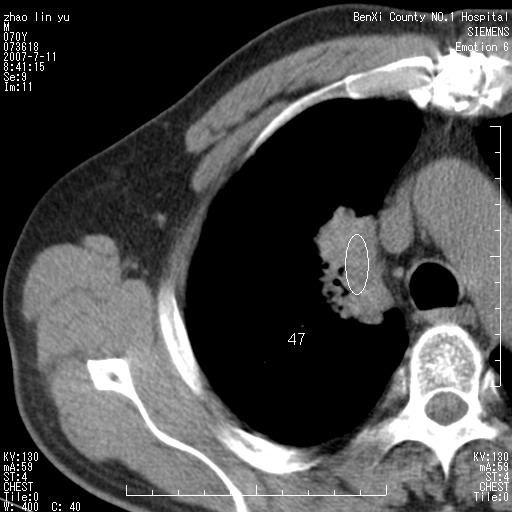

以下是引用王靖旗在2007-7-10 17:12:00的发言:[br] 男、70、咳嗽两个月,半年前换瓣手术,胸片未见异常,于昨天行x片发现右肺上野大片影,行ct扫描,这里是减薄图像,余肺正常。明天晚上会有增强扫描片,到时我会上传。[br][br] 冠状位请大家细看,应该是有意义的,[br][br] 请大家先看平扫发表意见。[br][br]

以下是引用zhangzhongshou在2007-7-10 21:43:00的发言:[br]右肺上叶周围型肺癌,以孤立型细支气管肺泡癌可能性大。